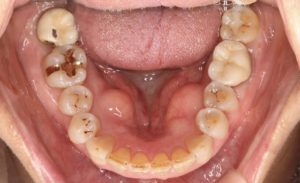

下のあごの内側にできものができたので診てほしいと来られた患者さん。

診察すると、下顎隆起という骨のコブで病気ではありませんでした。

将来義歯を作るときに問題があるかもしれませんが、当面は放置していても大丈夫です。